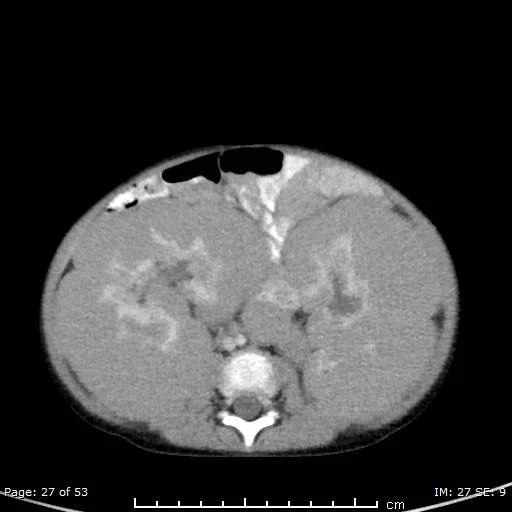

Wilms Tumor

• Rarely has calcifications

• Age ~4 yo (never seen before 2 months old)

• More commonly mets to lung & liver

• Does not invade spinal canal

• Retroperitoneal lymphadenopathy uncommon

• Claw sign

• Evaluate for renal/IVC thrombus or invasion

• Do not biopsy - will seed

• Variants

• Clear cell - likes to have lytic met to bone

• Rhabdoid - causes WHO 4 brain tumors - worse prognosis